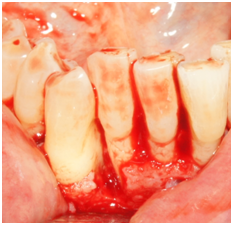

Phase I therapy was initiated and consisted of oral hygiene instructions and full mouth scaling and root planing under local anesthesia. Reevaluation was performed after 6 weeks to evaluate the periodontal treatment and the need for any further intervention. Phase II therapy was indicated and included regenerative surgery using enamel matrix derivative to treat the increased probing depth of 9mm and residual bony defect on the disto-palatal of tooth #7. The rationale for treatment was discussed with the patient. She was also informed of the regenerative material and its origin. Because the defect around tooth #7 was isolated, an endodontic consultation was performed and the likely absence of a root fracture or pulpal pathology was confirmed. No other contributory factors were noted at the examination. The patient was informed of the risk of tissue recession postoperatively as part of the written consent process. The patient was appointed to undergo surgical treatment that was carried out as follows: Local anesthesia utilizing 2% lidocaine with 1:100,000 epinephrine was administered at the site of the surgery followed by intrasulcular incisions from distal of tooth #5 to mesial of tooth #8. A full thickness mucoperioosteal flap was reflected both facially and palatally to give good access to the defect site. The bony defect was identified and all the granulomatous tissue was removed and the root surface was debrided with ultrasonic and hand instruments (Figure 2a & 2b). The intrabony defect was identified as a three-wall disto-palatal defect. The root surface was examined for any abnormality or fracture and none was noted. EDTA and enamel matrix derivative‡‡ were applied to the defect according to the manufacturer instructions. The flap was secured back with interrupted 4-0 chromic gut sutures. Post-operative instructions were given to the patient both written and verbally. The patient was instructed to take pain medication (ibuprofen) as needed and to use chlorhexidine 0.12% mouth rinse. The patient was seen one week post-operatively and the sutures were removed.

Figure 2a Palatal view of tooth #7. Reflection of a full-thickness flap showing the bony defect on the distal aspect.

Figure 2b Facial view of tooth #7. Reflection of a full-thickness flap showing the bony defect on the distal aspect.